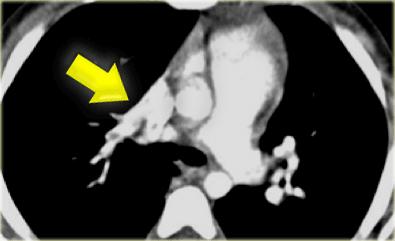

When there is a significant shunt, they may cause (late) pulmonary hypertension as seen in the case on the left.

The chest film in this adult shows large pulmonary arteries and a large right atrium and ventricle as a result of pulmonary hypertension.